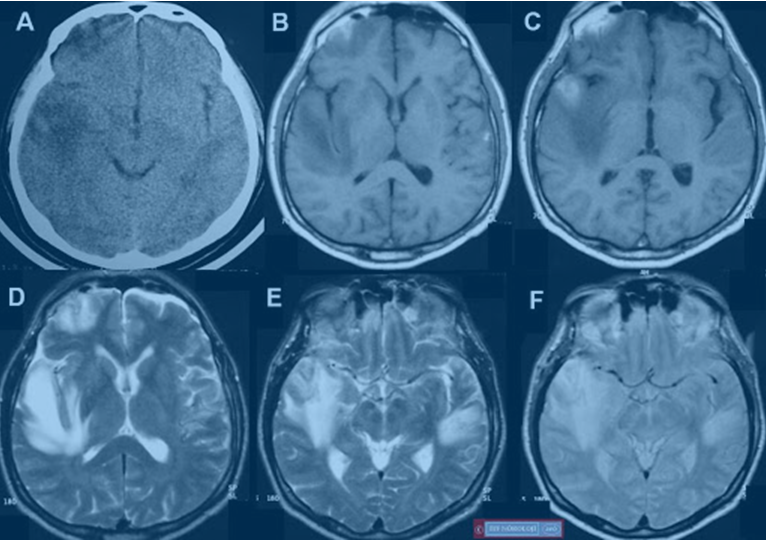

Ensefalit tanısının konmasında en önemli basamak hastanın şikayetlerinin ve nörolojik bulgularının değerlendirilmesidir. Bunu beyin görüntülemesi, tercihen ilaçlı beyin MR’ı izler. Sıklıkla kesin tanı için de beyin omurilik sıvısının (bel suyu incelemesi de gereklidir.